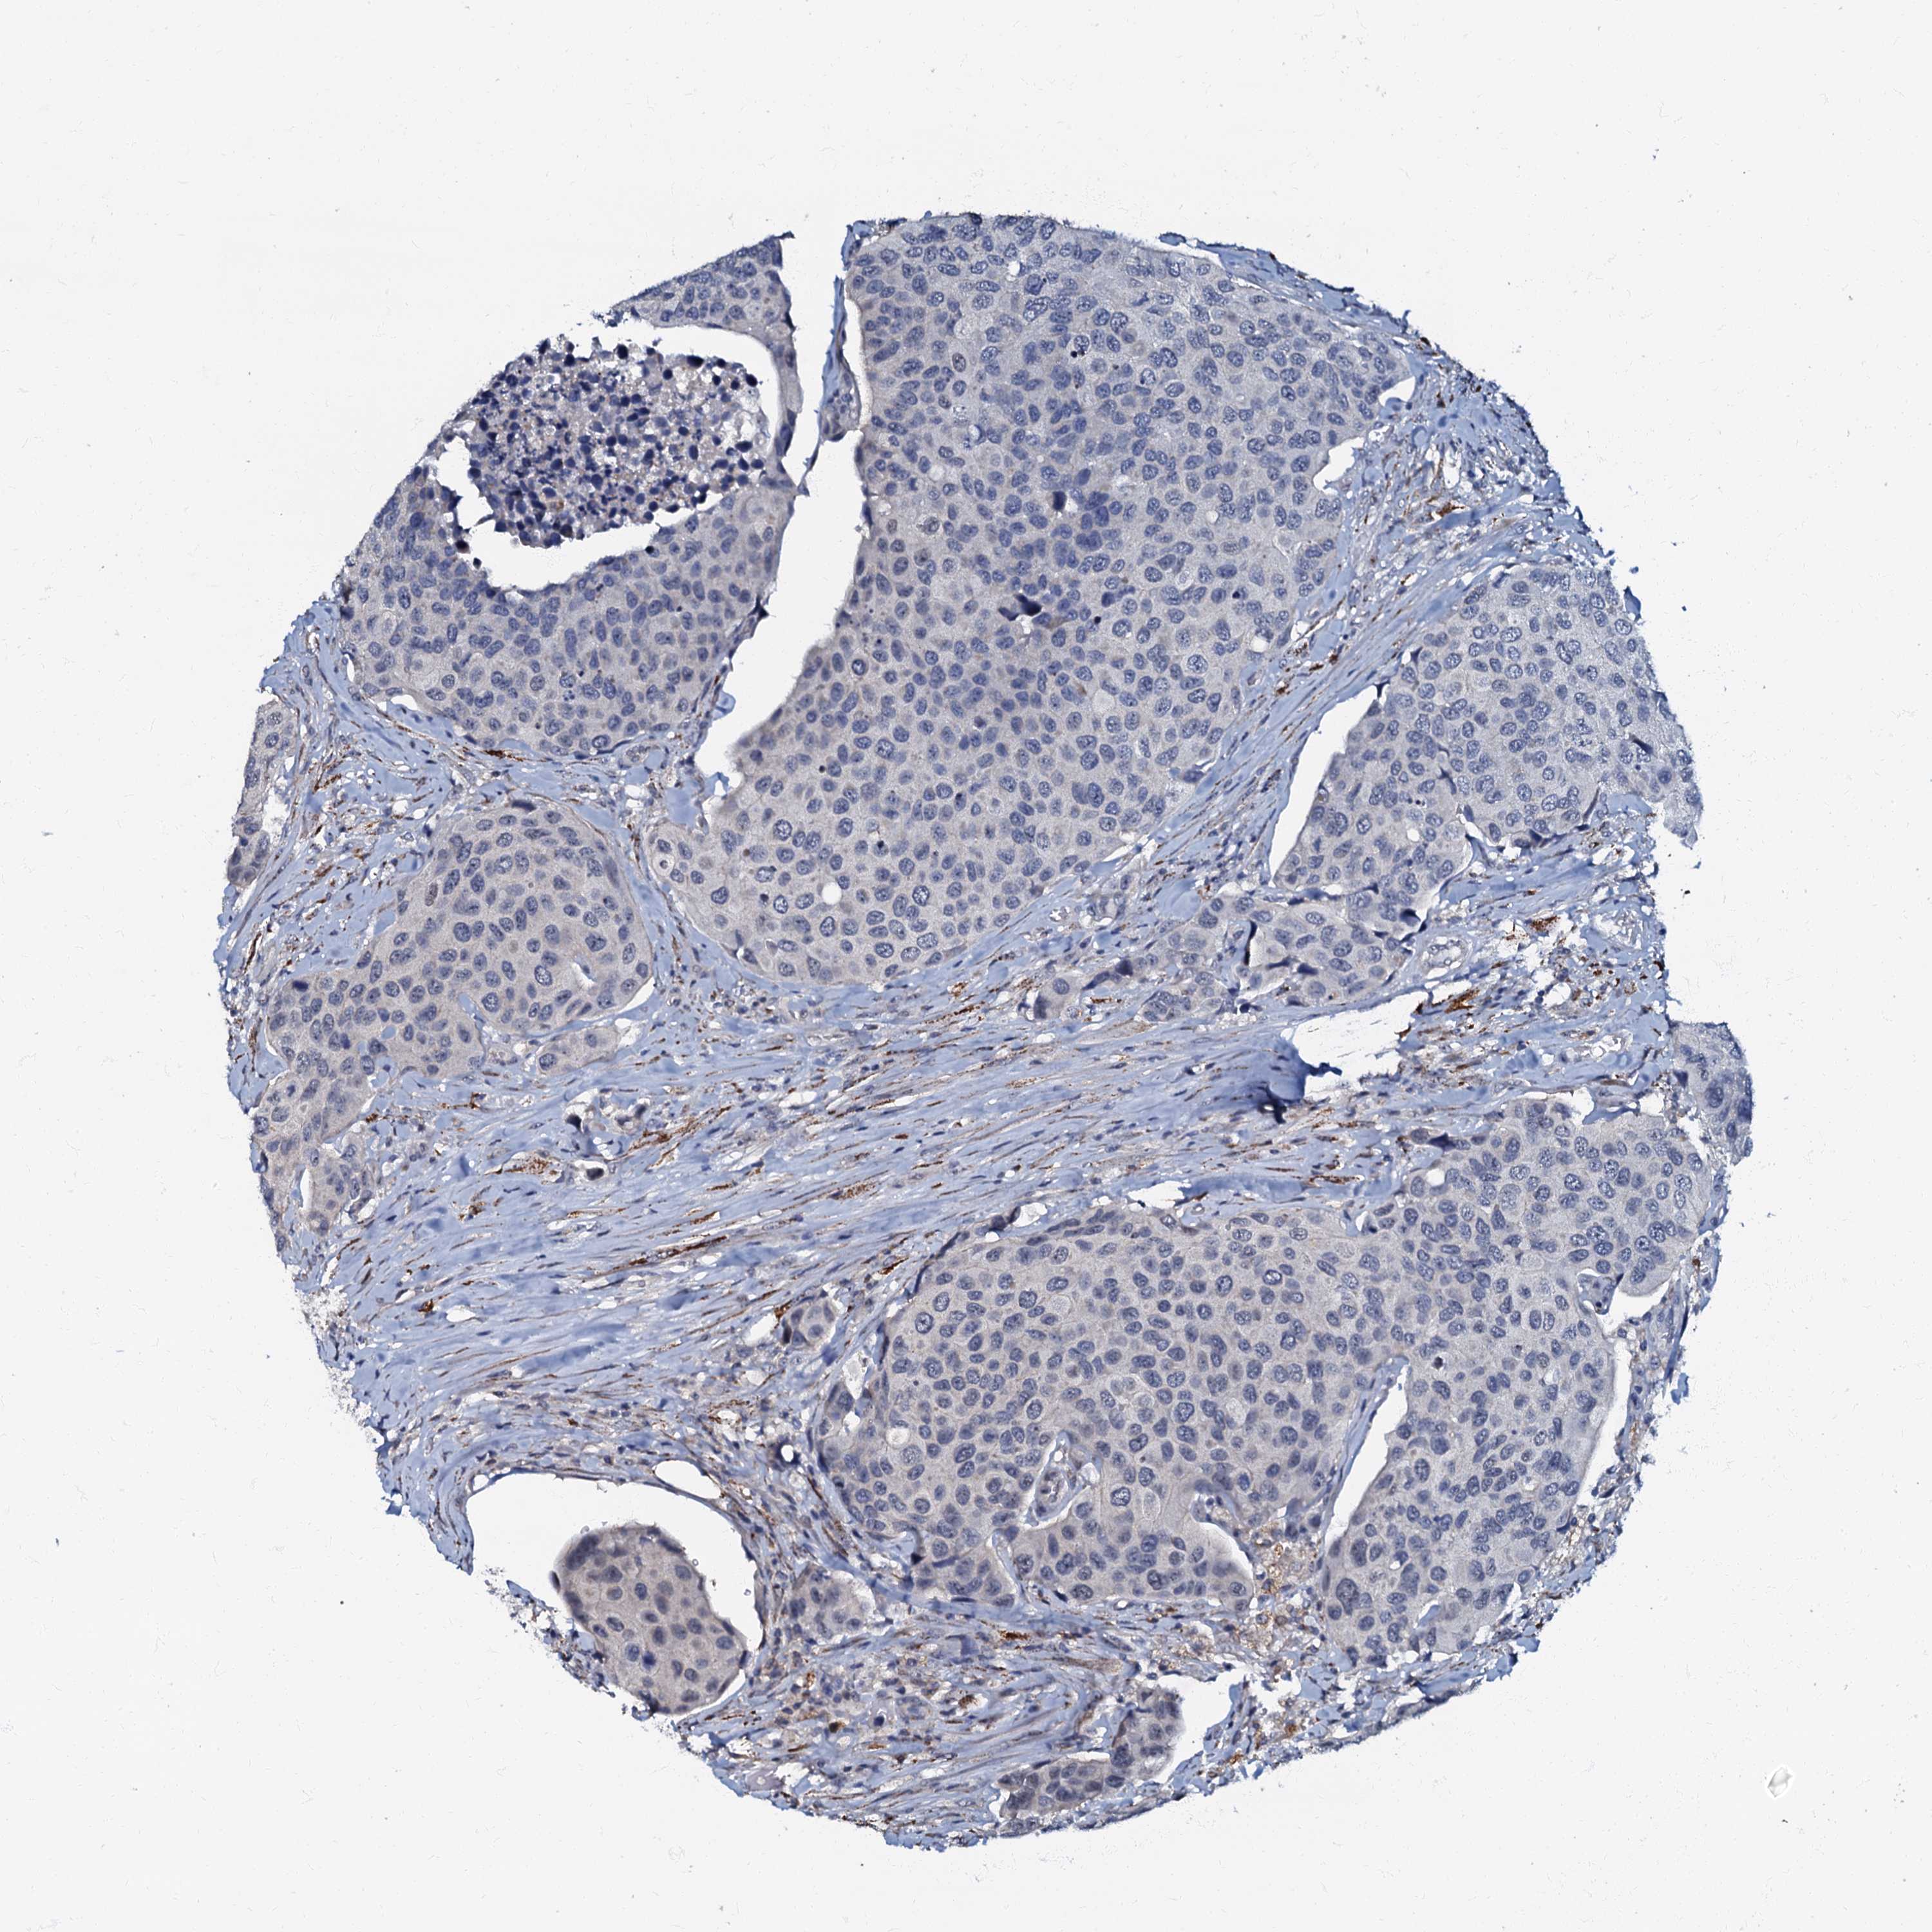

UROTHELIAL CANCER - Protein expressioni

A mouse-over function shows sample information and annotation data. Click on an image to view it in a full screen mode. Samples can be filtered based on level of antibody staining by selecting one or several of the following categories: high, medium, low and not detected. The assay and annotation is described here.

Antibody stainingi

Antibody staining in the annotated cell types in the current human tissue is reported as not detected, low, medium, or high, based on conventional immunohistochemistry profiling in selected tissues. This score is based on the combination of the staining intensity and fraction of stained cells.

Each image is clickable and will lead to virtual microscopy that enables deeper exploration of all samples and also displays staining intensity scores, fraction scores and subcellular localization as well as patient and tissue information for each sample.

Antibody HPA037947

Antibody HPA037948

Urothelial carcinoma, High grade

Urothelial carcinoma, Low grade

Urothelial carcinoma, NOS